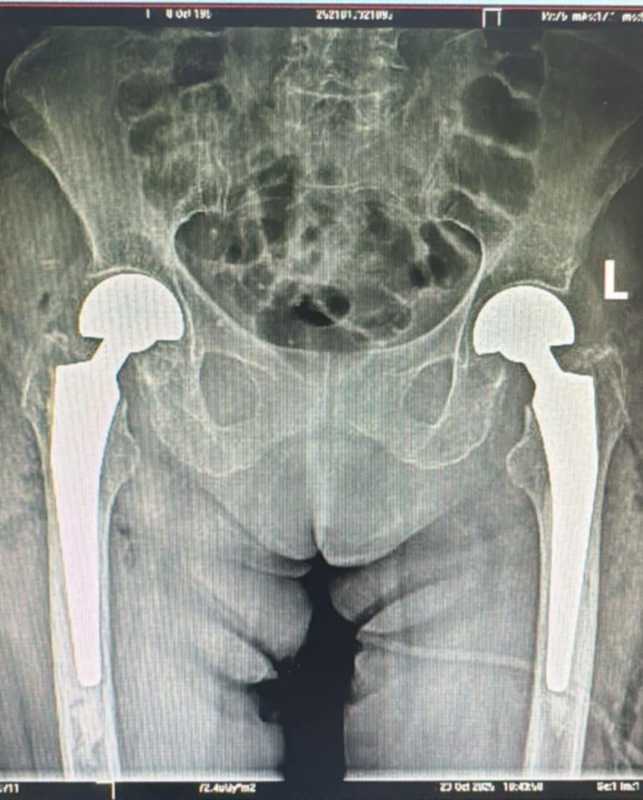

Foto: Spitalul Clinic Judeţean de Urgenţă Sibiu

'O intervenție medicală complexă și extrem de rar întâlnită a fost realizată în premieră la Spitalul Clinic Județean de Urgență Sibiu, unde echipa de ortopedie a efectuat o artroplastie parțială de șold bilateral, o procedură chirurgicală majoră, efectuată simultan pe ambele șolduri. Cazul a vizat o pacientă diagnosticată cu fractură bilaterală de col femural, o afecțiune severă care necesită intervenție rapidă și un grad ridicat de expertiză. Reușita operației confirmă capacitatea spitalului de a gestiona situații medicale deosebite și de a oferi pacienților tratamente avansate, realizate conform celor mai înalte standarde. Pacienta în vârstă de 73 de ani s-a prezentat în Unitatea Primiri Urgențe a Spitalului Clinic Județean de Urgență Sibiu acuzând dureri intense la nivelul membrelor inferioare și imposibilitatea de a se deplasa. În urma investigațiilor clinice și paraclinice imagistice, echipa medicală a diagnosticat o fractură bilaterală de col femural, o patologie severă și extrem de rar întâlnită', se arată în comunicat.

Echipa chirurgicală a realizat o procedură nouă într-un spital public din Sibiu: 'artroplastie parțială de șold bilateral, cu proteze bipolare cimentate, efectuată în același timp operator.'